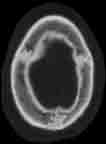

Visible Human male: Sectio transversalis 1025

CT

NMR

Pd T1 T2